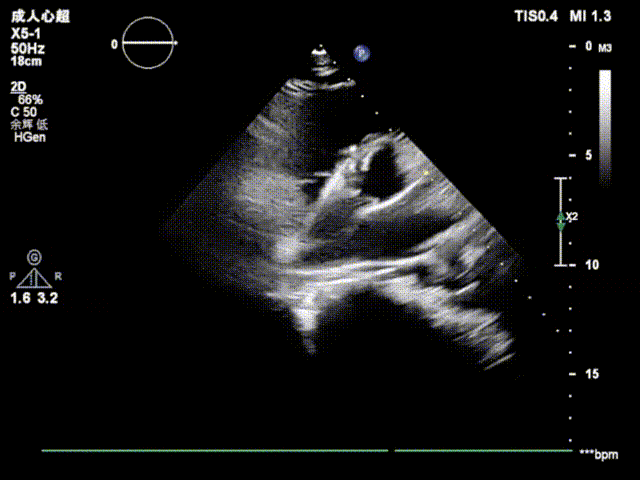

后在TTE指导下,术者按照标准操作流程先释放封堵器左盘,牵拉成型线,使封堵器左盘由纺锤形变成“圆盘形”;后释放右盘,经二次成型,使封堵器骑跨缺损两侧,紧贴室间隔,锁定成型线。

上:左盘释放成型;下:右盘释放成型、双盘骑跨缺损两侧

经牵拉测试,封堵器位置形态稳定,对瓣膜功能无影响,故完全释放封堵器。

复查超声及造影提示封堵器位置形态稳定,无残余分流,手术圆满成功!